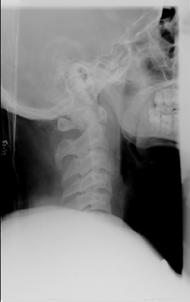

TRAUMA CERVICALA

Incidenta laterala Incidenta

laterala Incidenta

antero-posterioara

Aspect normal Imagine

incompleta Aspect

normal

Incidenta occipitomentala (odontoida)

Aspect normal Incidenta

oblica

Aspect normal

Incidenta oblica Incidenta laterala Incidenta antero-posterioara

Aspect normal Aspect normal Aspect normal